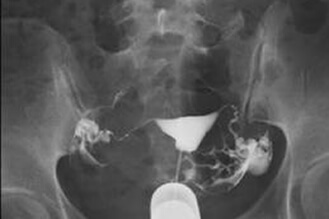

Normal salpingography,bilateral patent fallopian tubes

bilateral fallopian tubes swollen and blocked